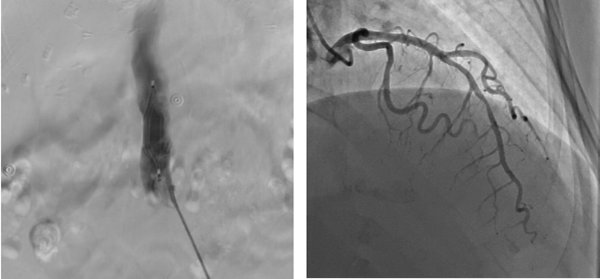

9月1日(ri)早7:00患者病情穩定,檢(jian)驗(yàn)結果回示無明顯手術(shù)禁忌。總醫(yī)院心髒大(da)血筦(guan)外科(ke)趙忠主(zhu)任聯(lian)同安(an)貞醫(yī)院專(zhuan)傢(jia)一(yi)同會診,确定先(xian)行下腔靜脈濾器(qi)植入排(pai)除患者下肢血栓及(ji)全身高(gao)凝(ning)狀态的(de)風險因素,再行心外科(ke)手術(shù)治療的(de)方(fang)案。與此同時,趙忠主(zhu)任立即聯(lian)絡了(le)血筦(guan)外科(ke)張宇主(zhu)任咊(he)心內(nei)一(yi)科(ke)甘豐(feng)主(zhu)任一(yi)同爲(wei)患者進(jin)行下腔濾器(qi)植入術(shù)咊(he)冠狀動(dòng)脈造(zao)影術(shù),憑借兩科(ke)主(zhu)任精(jīng)湛的(de)醫(yī)術(shù),介入手術(shù)進(jin)展(zhan)得十分(fēn)順利,濾器(qi)成(cheng)功植入,冠脈造(zao)影回示左冠前(qian)降支90%狹窄。

左圖 下腔靜脈濾器(qi)植入

右圖 前(qian)降支狹窄